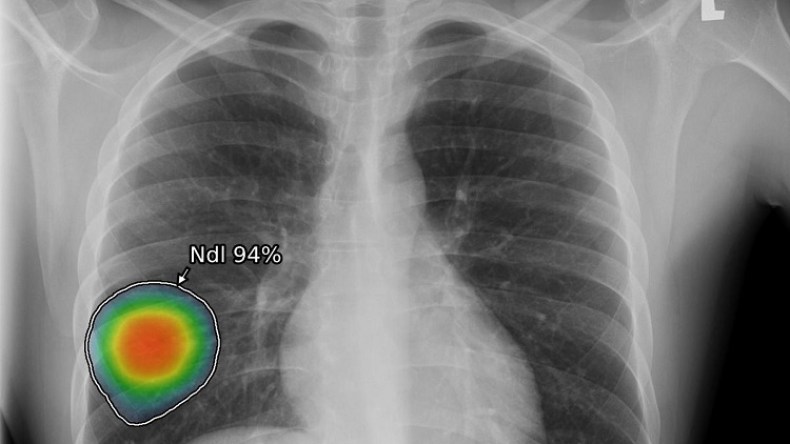

قدمت “جنرال إلكتريك للرعاية الصحية”، الأربعاء، “منظومة العناية الصدرية”، وهي مجموعة برمجية من ثماني خوارزميات للذكاء الاصطناعي قائمة على حلول “لونيت إنسايت”لتصوير الصدر بالأشعة السينية، وتساعد في تخفيف المضاعفات السريرية الناجمة عن مرض “كوفيد19”.

وتعمل المنظومة المدعومة بالذكاء الاصطناعي على تحليل نتائج التصوير بالأشعة السينية بسرعة وتكشف لأطباء الأشعة وجود أي مظاهر غير طبيعية وتمكنهم من مراجعة النتائج بدقة بما في ذلك احتمال وجود الالتهاب الرئوي، والذي قد يكون دليلاً على احتمال الإصابة بمرض “كوفيد-19″، علاوة على مرض السل والتعقيدات الرئوية وغيرها من الأمراض التي تكشفها نتائج التصوير الشعاعي.

وتستفيد “منظومة العناية الصدرية” من قوّة الذكاء الاصطناعي للمساعدة في الحد من هذه الضغوطات من خلال تحليل تلقائي للصور يرصد ثماني نتائج غير طبيعية للتصوير الشعاعي، بما في ذلك الاشتباه بالإصابة بمرض السل والالتهاب الرئوي، وهي أعراض يمكن أن تشير أيضاً إلى الإصابة بمرض “كوفيد-19”. وعند قراءة التقرير في أنظمة أرشفة الصور وأنظمة الاتصالات  (PACS)، يمكن للمتخصصين في التصوير الشعاعي التعرف بسرعة على حدة الأعراض غير الطبيعية الثمانية المحتملة، وإجراء عملية تركيب الصور، ووصف موقع الإصابة كتابياً بما يثمر في تسريع وتيرة التشخيص والعلاج.

وإضافة إلى الكشف عن الالتهاب الرئوي، تدعم “منظومة العناية الصدرية” أمراضاً مثل السل؛ وانخماص الرئة؛ والتكلس؛ وتضخم القلب؛ والتليف؛ واتساع المنصف؛ والعقيدات الرئوية؛ وكشف الانصباب الجنبي.